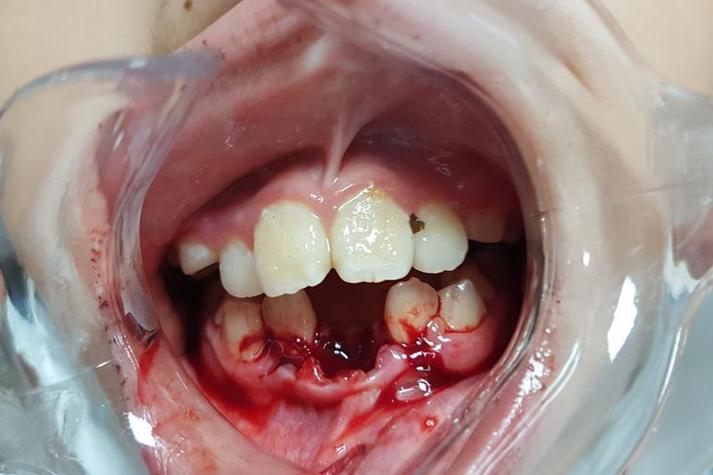

牙周组织是牙齿的“土壤”,若存在未经治疗的牙周炎、牙槽骨吸收等问题,牙根周围的支持骨量已不足,正畸加力会进一步加剧骨吸收,导致牙齿松动甚至脱落,临床中,部分患者因忽视牙龈出血、牙床萎缩等症状,未在正畸前完善牙周治疗,直接开始矫正,这种“带病矫正”是牙齿脱落的高危因素,中度牙周炎患者的牙槽骨吸收可能超过根长1/3,牙根周围骨壁变薄,正畸中轻微加力即可造成骨组织不可逆损伤,牙齿失去支撑后脱落。

牙齿移动需遵循“生物力学原则”,力的大小、方向、作用时间需严格控制,若医生经验不足,施加过大的力或移动速度过快,会打破牙槽骨改建的平衡:牙根周围的破骨细胞过度活跃,骨吸收速度超过骨形成速度,导致牙根与牙槽骨之间出现“间隙”,牙齿松动度增加;严重时可能直接损伤牙根表面,导致牙根吸收(根尖吸收、根侧吸收),牙根长度缩短,支持力下降,最终脱落,在关闭拔牙间隙时,若使用强支抗力量直接拉尖牙,未考虑牙根形态和骨密度,可能导致尖牙牙根吸收1/3以上,牙齿松动度达Ⅲ度,最终无法保留而拔除。

正畸患者需佩戴托槽、弓丝等矫正装置,食物残渣易堆积,若刷牙不彻底,会迅速形成牙菌斑和牙结石,诱发牙龈炎、牙周炎,牙龈炎会导致牙龈红肿、出血,牙周炎则进一步破坏牙槽骨,使牙齿支持组织减少,正畸装置本身可能刺激牙龈,若口腔卫生差,局部炎症反应加剧,牙齿在移动过程中更容易因感染而松动脱落,研究显示,正畸患者中牙龈炎发病率高达60%-90%,若未及时干预,3年内牙槽骨吸收风险增加3倍。

明显松动(Ⅲ度松动,或伴牙根吸收)

需立即停止正畸治疗,拍摄根尖片和CBCT评估牙根吸收程度和骨缺损情况,若牙根吸收<1/3,松动度可逆,可进行牙周固定(如树脂夹板固定),并密切观察;若牙根吸收≥1/3或骨缺损严重,牙齿支持力丧失,需拔除患牙,待正畸结束后再考虑种植义齿或修复体修复。